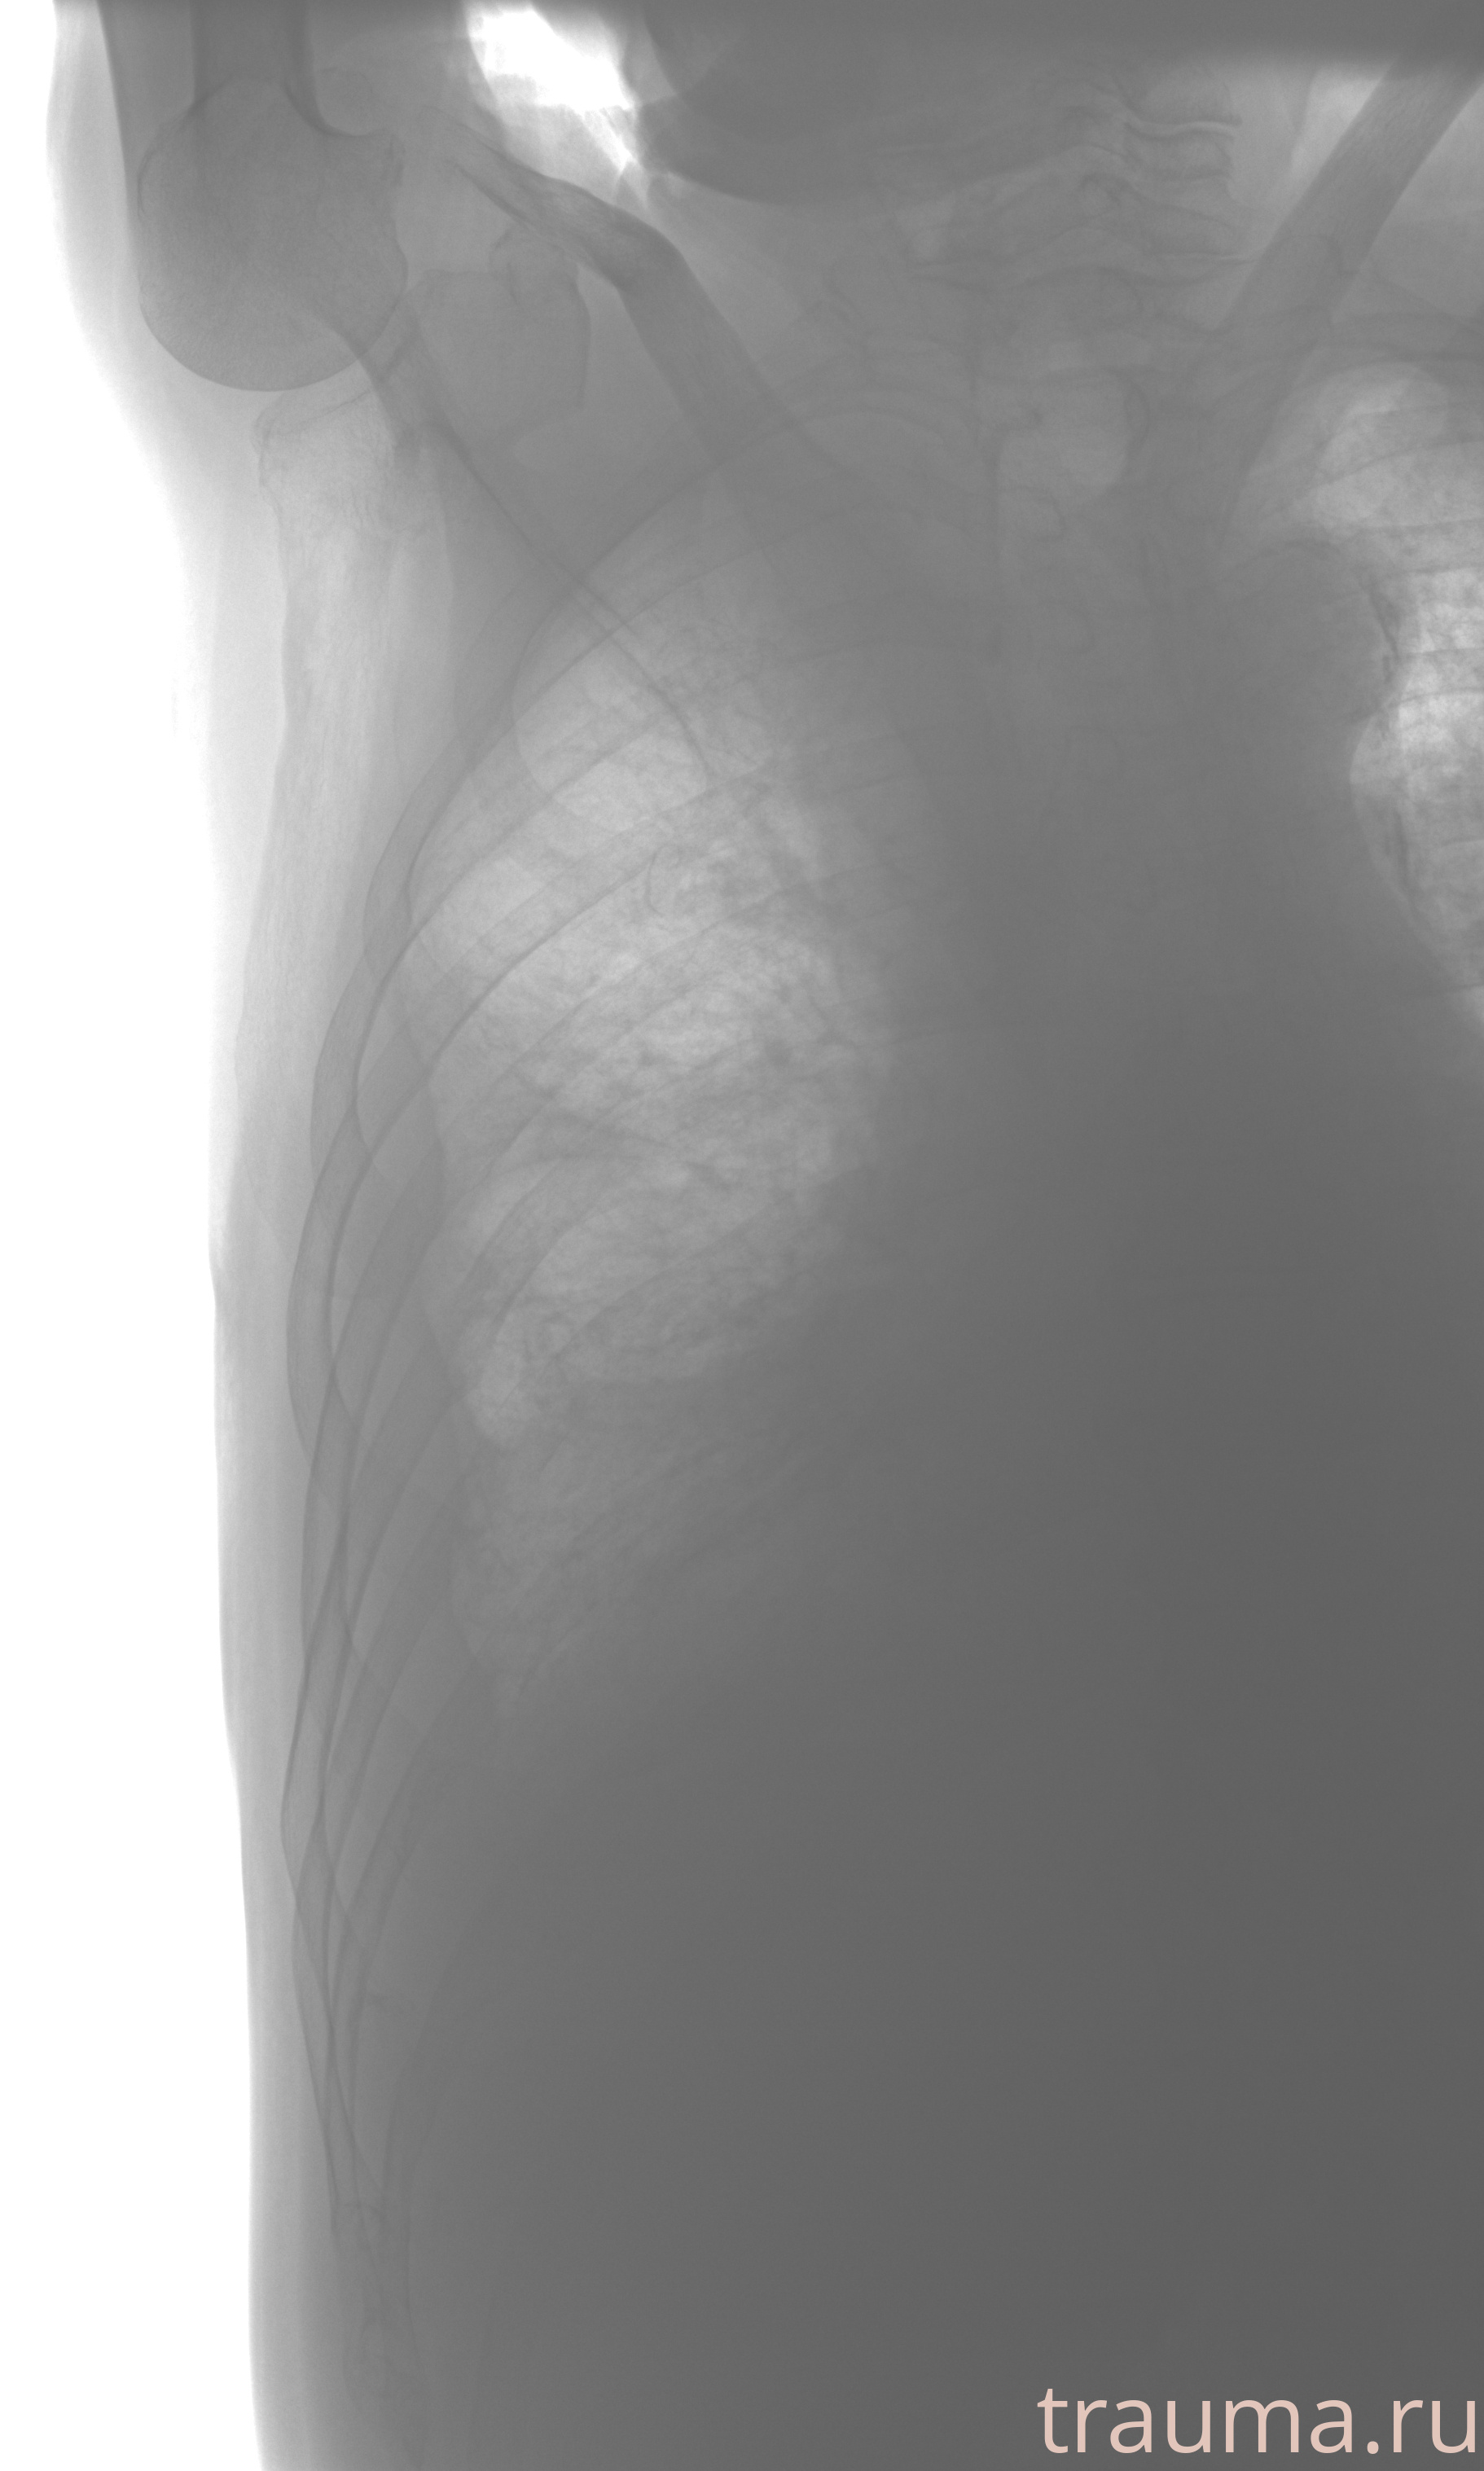

Рентген на дому: по вашему адресу приезжает врач-рентгенолог, травматолог-ортопед с мобильным рентгеновским аппаратом, проводит диагностику травмы или заболевания, делает необходимые рентгенограммы, дает рекомендации по дальнейшему лечению. Получить качественные снимки в домашних условиях возможно благодаря уникальной методике, разработанной МосРентген Центром для института  Склифосовского

при переломе шейки бедра и пневмонии от компании МосРентген Центр - партнера Института имени Склифосовского